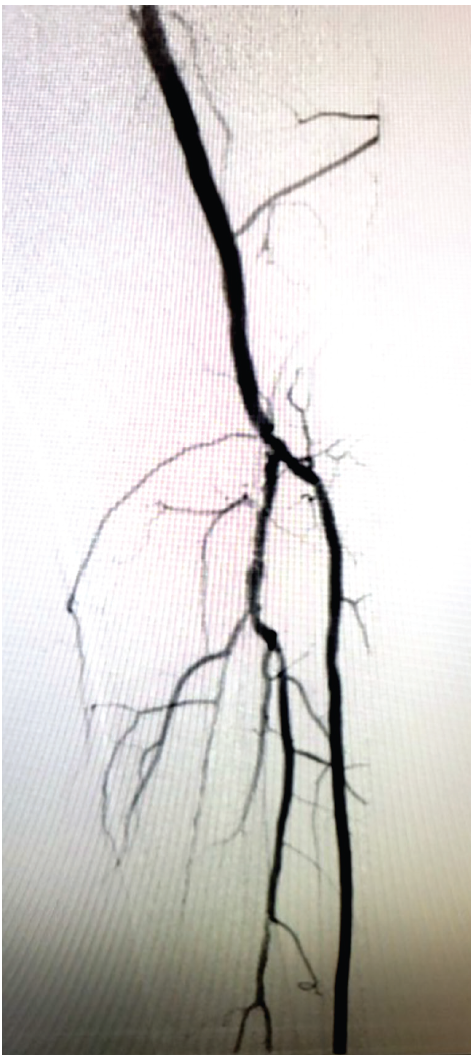

Several prolonged balloon inflations of the proximal, mid, and distal right SFA were performed. There was a residual, >50% stenosis and flow- limiting dissection, so a 6 mm x 200 mm nitinol stent was deployed in the distal right SFA. A 6 mm x 120 mm nitinol stent was deployed proximal to the first stent. The stents were post-dilated with a 6 mm x 100 mm balloon. Selective angiography showed an excellent result. There was no dissection, no thrombus, and improved distal runoff. At that point, all catheters and wires were removed. An Angio-Seal device (Terumo Interventional Systems) was used for closure of the right common femoral arteriotomy site. A ProGlide device (Abbott) was used for closure of the left common femoral arteriotomy site.

The patient followed up with podiatry and underwent hyperbaric therapy for the right foot wound. After several months, he demonstrated complete wound healing.